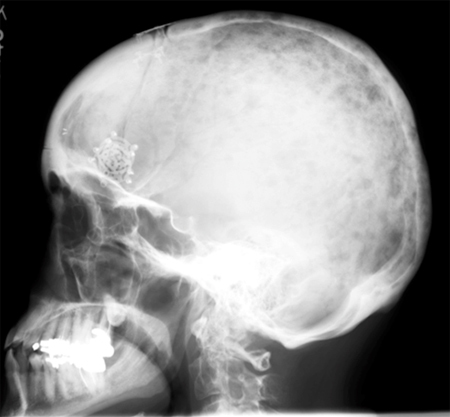

Evaluation of monoclonal gammopathies

Myeloma bone disease

From the personal collection of Dr Kumar